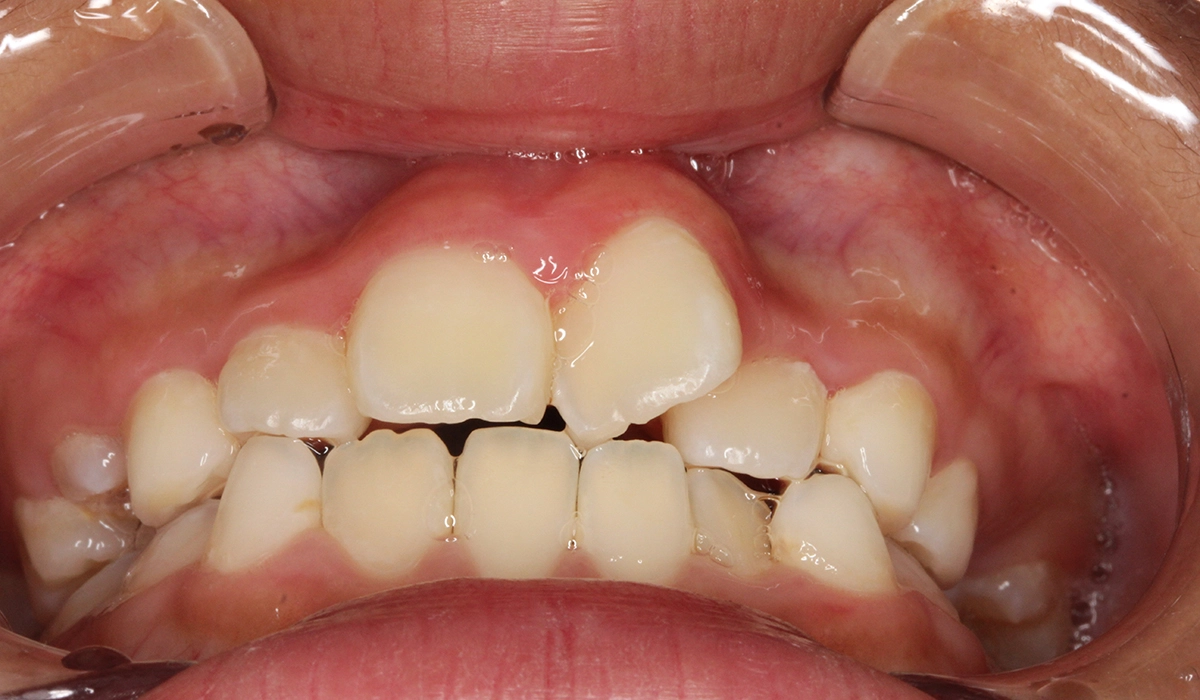

今回ご紹介する患者様は、前歯の捻れを気にされており、矯正検査後叢生Ⅰ級と診断いたしました。

術前:正面

主訴 前歯の捻れが気になる

治療期間 70カ月

治療費用 453,600円(税込)※2019年時治療費

治療内容 前歯の捻れを気にされており、矯正検査後叢生Ⅰ級と診断いたしました。